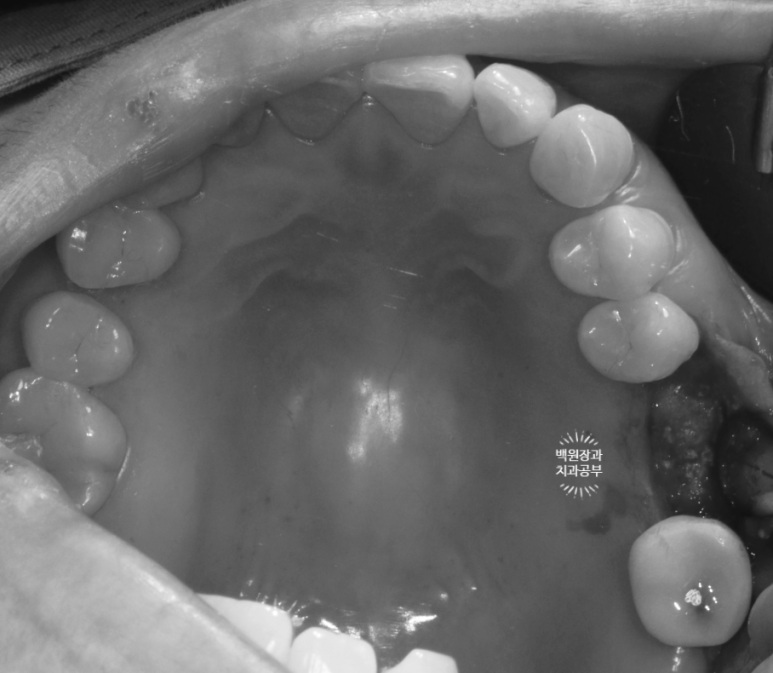

처음 오셨을 때 입 안 사진으로 보면, PFM 크라운 두 개가 붙어있는 형태.

즉, splinted PFM crown 형태로 제작이 되어 있었어요.

3개월의 치유기간을 가진 후 보시는 바와 같이 새로이 보철물을 제작해 드렸습니다.

약간 이상적이지 않은 형태 같아 보이실 수 있지만!?

입안에서 본 사진 상에서는 상당히 이상적인 지르코니아 크라운 형태로

제작이 잘 되었다는 것 !!